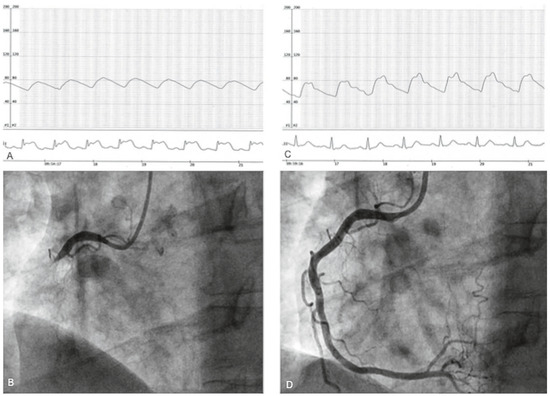

A 50-year-old man, hypertensive and an active smoker, had for many years been complaining of typical chest pain, which occurred most often upon wakening in the morning. Recently prescribed sublingual nitrate relieved the chest pain. Coronary angiography was performed at 9:00 a.m. via a right transradial approach and with 5 Fr diagnostic catheters (Judkins left 3.5 and Judkins right 4.0). At the end of straightforward left coronary injections, which did not show significant coronary stenosis, he experienced his usual intense chest pain with major ST-segment elevation on the monitor (Figure 1A) and subsequent transient complete atrioventricular block. Prompt injection of the right coronary artery (RCA) showed a proximal occlusion (Figure 1B). After sublingual nitrate administration, chest pain progressively disappeared, the ECG normalised (Figure 1C) and the RCA was again open without any significant stenosis (Figure 1D). A daily calcium antagonist was prescribed with sublingual nitrate as needed. Smoking cessation was highly recommended. At the 18-month follow-up the patient was no longer a smoker and still free of cardiac symptoms under chronic medication.

Figure 1. Explanation in text.